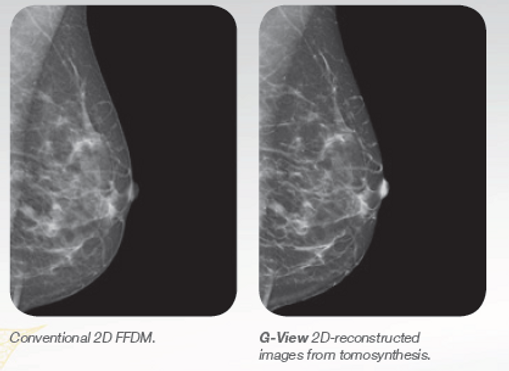

G-VIEW Synthesized image from 3D to 2D

​The new integrated G-View software allows the reconstruction of a standard mammography projection from the 3D Tomosynthesis images data set. The G-View 2 image is generated without the need an extra 2D mammography exposure, so using the generated synthesized 2D image instead of the current 2D plus 3D image, it drastically reduces the patient’s radiation exposure and compression time. You can review the G-View projections after Tomosynthesis exposure in just a few seconds, with a simple click.